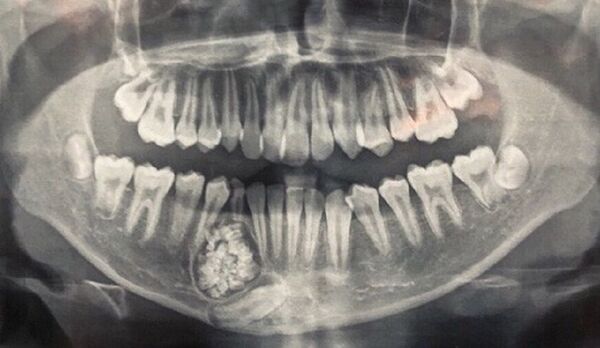

Qua chụp X-quang các bác sĩ của BV Khánh Hòa bất ngờ phát hiện có 1 khối u răng ở xương hàm dưới.

Theo bác sĩ Tuấn, u răng (hay còn gọi Odontoma) là một trong những loại u lành tính. U răng rất khó phát hiện, chỉ qua phim chụp X-quang mới có thể nhìn thấy. Nhiều bệnh nhân không phát hiện sớm và điều trị kịp thời dẫn đến u tiến triển lớn, gây khó khăn trong điều trị và có thể gây ra các biến chứng không mong muốn như gây gãy xương hàm bệnh lý, tổn thuơng đứt dây thần kinh...